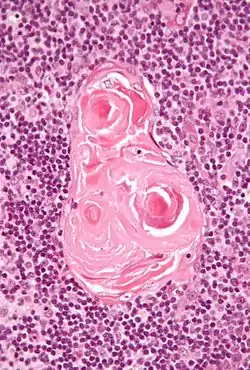

In the medulla, the network of epithelial cells is coarser than in the cortex, and the lymphoid cells are relatively fewer in number.[1] Concentric, nest-like bodies called Hassall's corpuscles (also called thymic corpuscles) are formed by aggregations of the medullary epithelial cells.[3] These are concentric, layered whorls of epithelial cells that increase in number throughout life.[1] They are the remains of the epithelial tubes, which grow out from the third pharyngeal pouches of the embryo to form the thymus.[6]

Micrograph showing a Hassall's corpuscle, found within the medulla of the thymus.